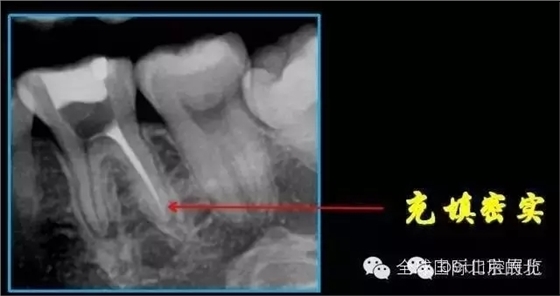

終于找到MB了,然后把根管口MM,ML封閉,S3機擴,F1.04錐度牙膠試尖,期盼了好久的柳暗花明終于出現。

終于完成根充

MM,ML其實融合為一個根管口的,截面就是三根管的形態(tài),然后做了一個簡單清晰的三維重建,形態(tài)還是挺不錯的 。 一個月后復查,如果無明顯反應就進行及時的冠修復,做好冠方封閉 以后3-6個月再做跟蹤回訪